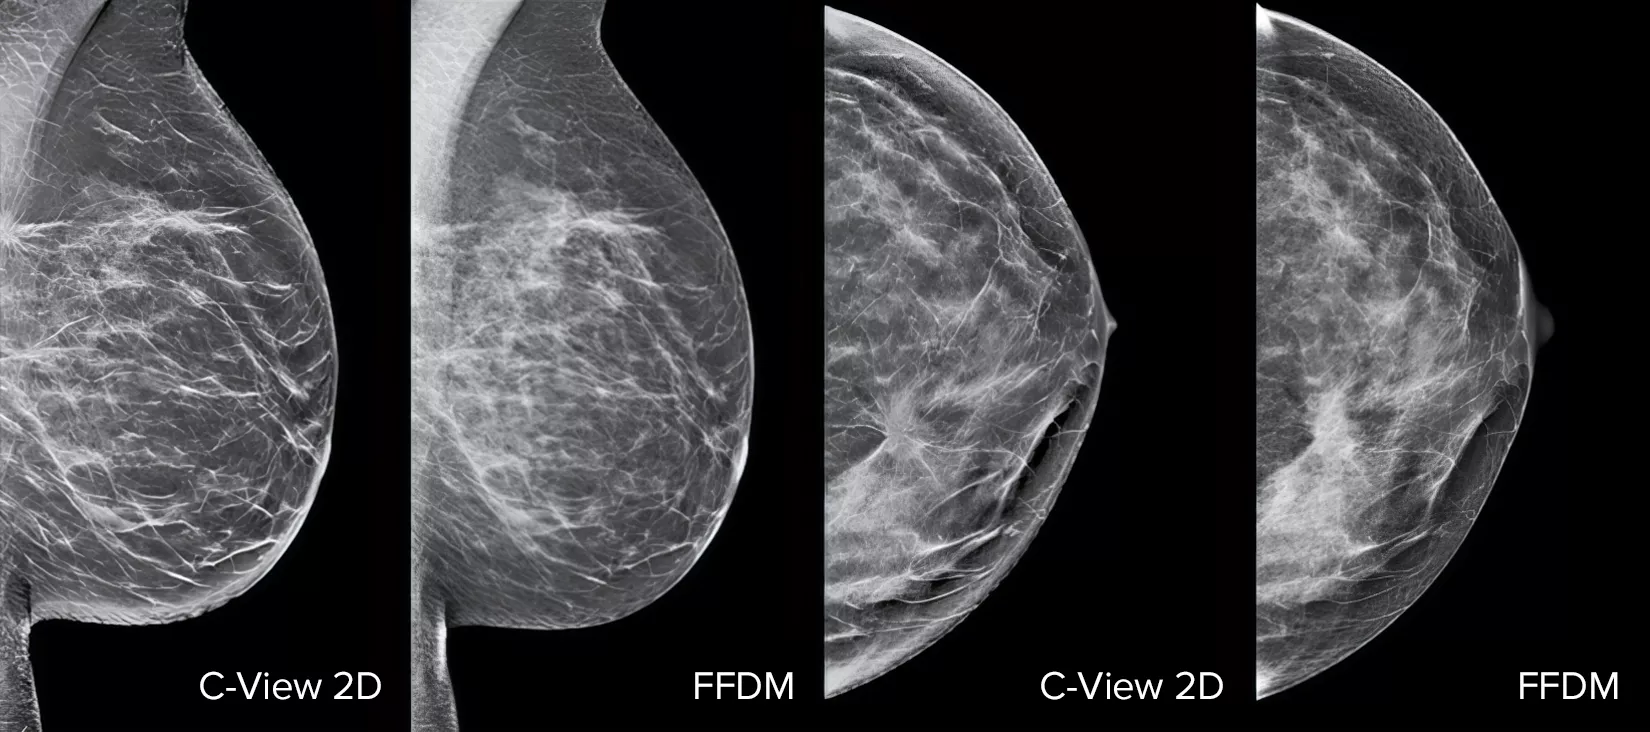

Melhore o seu desempenho em rastreio do cancro da mama1-4 com o software C-View e obtenha imagens 2D sintetizadas instantâneas. Este não só torna os detalhes mais visíveis e torna a análise mais rápida, como também reduz os níveis de dose de radiação a que os pacientes estão expostos. As imagens 2D do C-View estão clinicamente comprovadas3,5 e têm a aprovação da FDA para substituírem as imagens FFDM no diagnóstico em contexto de exame de rastreio de tomossíntese.

As anomalias estruturais, as lesões de massa e pontos brilhantes normalmente detetados nas microcalcificações são mais visíveis na imagem 2D do C-View do que nas imagens tradicionais 2D FFDM ou nos cortes tomográficos.4,6-9

A prova está nos detalhes

As imagens 2D do C-View estão clinicamente comprovadas3,5 e têm a aprovação da FDA para substituírem as imagens FFDM no diagnóstico em contexto de exame de rastreio de tomossíntese. Os estudos publicados mostram que o exame 3D Mammography de dose baixa deteta o cancro invasivo mais precocemente, em comparação com o 2D por si só, ao mesmo tempo que reduz as taxas de reincidência de falsos positivos.4,5,7

As anomalias estruturais, as lesões de massa e pontos brilhantes normalmente detetados nas microcalcificações são mais visíveis na imagem 2D do C-View do que na imagem tradicional 2D FFDM ou no corte tomográfico.4,6-9

Imagens de vários raio-X mamários